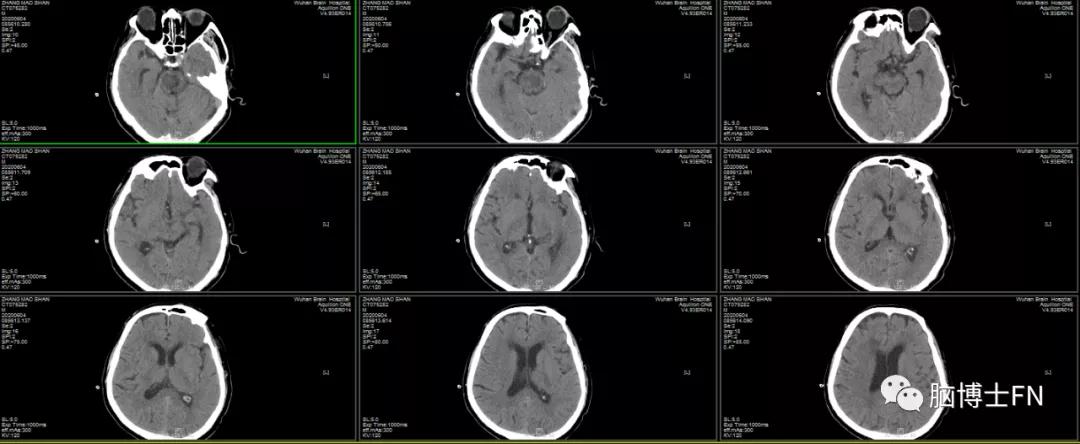

出院头部CT